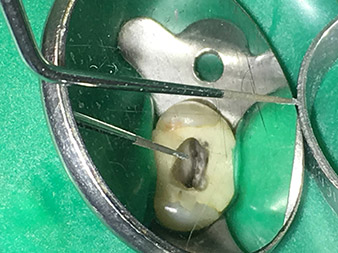

Die Spitze 2E dient der lateralen Kondensation. Bei dieser Abfülltechnik wird nach Anpassung des MasterPoints im Kanal die Guttapercha lateral durch das Einführen des Instruments verdichtet, sodass Platz für weitere Spitzen entsteht. Die nächste Spitze wird dann erneut in den Kanal eingebracht und erneut verdichtet oder „kondensiert“. Dieser Vorgang wird mehrmals wiederholt bis der Kanal abgefüllt ist.

Alternativ kann man bei WF-Revisionen das Instrument - sofern die Kanalanatomie und Voraufbereitung es erlauben - in den Kanal einführen und durch die Hitze, die bei der Aktivierung entsteht, die Guttapercha minimal erweichen, sodass die Entfernung im koronalen Abschnitt erleichtert wird.